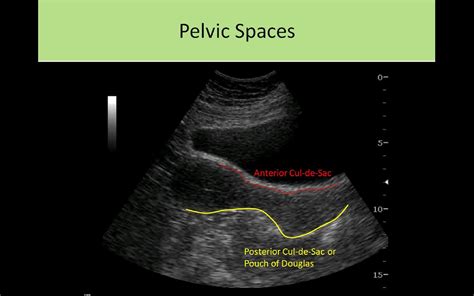

The Posterior Cul De Sac is a small, pouch-like structure found at the end of the rectum. It is part of the larger cul-de-sac system, which includes the anterior and lateral cul-de-sacs. The posterior cul-de-sac is particularly important because it is the lowest point in the pelvic cavity, making it a critical area for the accumulation of fluids and waste materials.

Diagnosing conditions affecting the Posterior Cul De Sac often involves a combination of medical history, physical examination, and diagnostic tests. Some of the most common diagnostic techniques include:

• Colonoscopy: A colonoscopy is a procedure in which a flexible tube with a camera is inserted into the rectum to visualize the entire colon and rectum. This test can help identify polyps, tumors, and other abnormalities in the Posterior Cul De Sac.